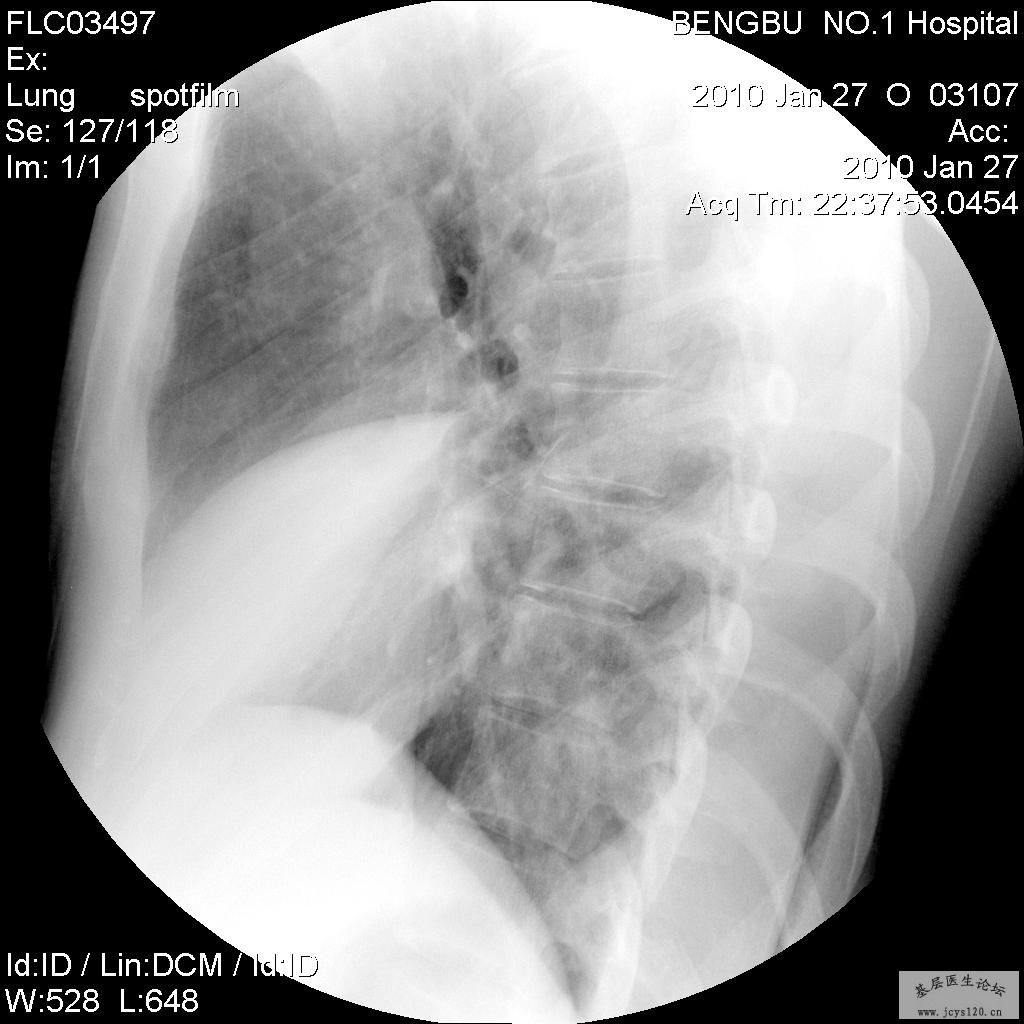

患者75岁,男性,近十年以来反复右侧胸部中下反复不规则疼痛有时放射到肩胛内侧,自觉有东西压在里面;季节交界、晚间尤甚。据说有过外伤史。今天拍了DR,片子如下正侧片.麻烦各位老师帮忙看看片. 阅读全文>